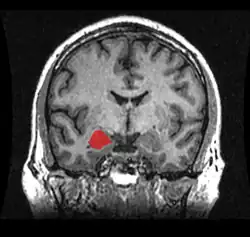

Cuerpo amigdalino

El cuerpo amigdalino, complejo amigdalino o amígdala cerebral es un conjunto de núcleos de neuronas localizadas en la profundidad de los lóbulos temporales de los vertebrados complejos, incluidos los humanos.[1] La amígdala forma parte del sistema límbico, y su papel principal es el procesamiento y almacenamiento de reacciones emocionales.[2][3]